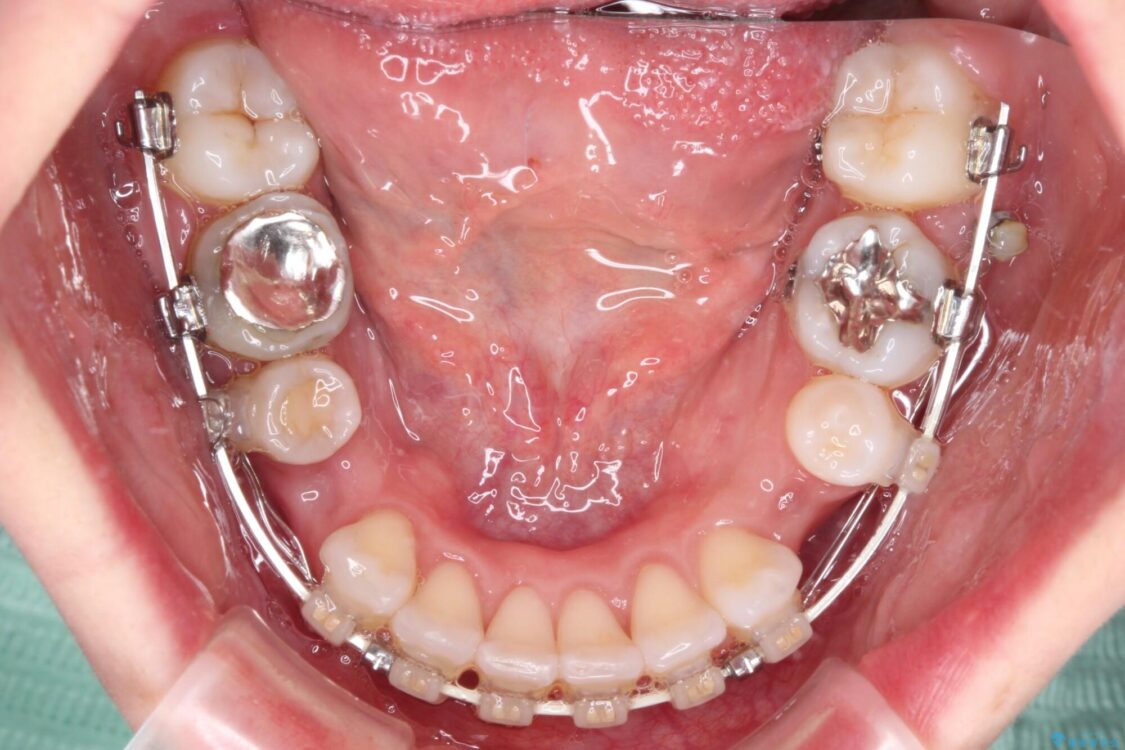

左下の大臼歯2本が顕著に舌側に傾斜しているため、まずは奥歯の咬み合わせを改善をし、その後上下左右の第1小臼歯4本を抜歯することで口元を引っ込めながら整えることとしました。

治療途中

• 【モニター】出っ歯と咬み合わせを改善 ワイヤー装置の抜歯矯正 治療途中画像

奥歯の咬み合わせ改善には1年ほどの期間と処置中の噛みにくさを強いることとなりましたが、抜歯後はスムーズに治療を完了させることができました。